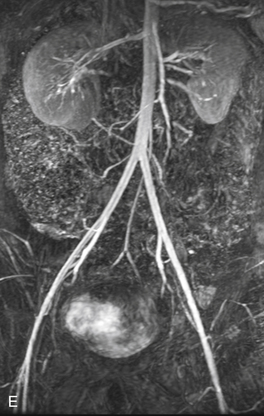

РИСУНОК 13-9. А. Брюшная аорта (Ао) заканчивается разветвлением на общие подвздошные артерии (CI) на уровне позвонка L4. Б. Общие подвздошные артерии делятся в пояснично-крестцовом соединении на внутреннюю (II) и наружную подвздошную (EI) артерии. Внутренняя подвздошная артерия (также называемая подчревной артерией) снабжает внутренние органы и мускулатуру таза. Ветви этой артерии становятся важными сопутствующими путями, как видно на других рисунках. Наружная подвздошная артерия переходит в общую бедренную артерию у паховой связки, как показано на рисунке 13-10 . C : Трехмерная объемная (VR) компьютерная томографическая (КТ) ангиограмма аорты и сегмента подвздошно-бедренной артерии. D. Проекция максимальной интенсивности (MIP) КТ-ангиограммы подвздошно-бедренных сегментов демонстрирует очаговые кальцификации в открытых сосудах. E — магнитно-резонансная ангиограмма (МРА) с усилением гадолинием аорты, подвздошного и бедренного сегментов. Анатомия наглядно иллюстрируется методами трехмерной реконструкции. С, чревная артерия; H, печеночная артерия; НМА, нижняя брыжеечная артерия; R, левая почечная артерия; рРГ – замена правой печеночной артерии; S, селезеночная артерия; СМА, верхняя брыжеечная артерия.